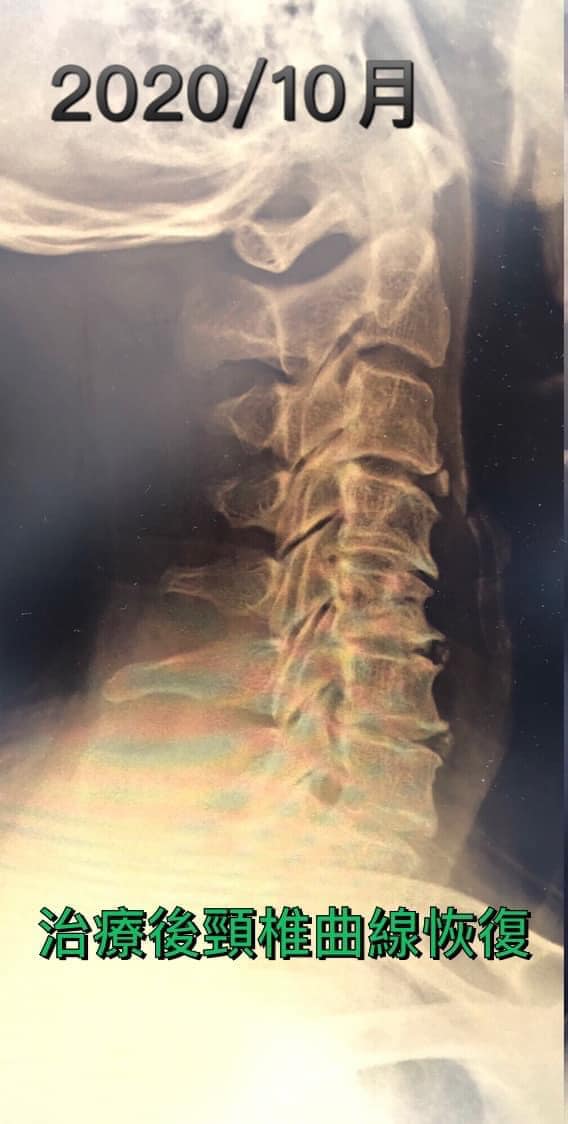

💯治療影片訪談:109/9/5~11/28總共14次治療

「三周的治療疼痛改善五成,之後信心大增,治療第四周後麻的程度明顯下降,治療第六周後腳的情況也有改善,最明顯的是肩膀疼痛完全消失」

他非常認真的接受微針減壓療法!更重要的是他卯起來做毛巾操跟收下巴運動,每天超過五百次以上,堅持了兩個多月,看到令人感動的片子,可以說頸椎反弓現象消失了,當然患者臨床症狀也改善很多。